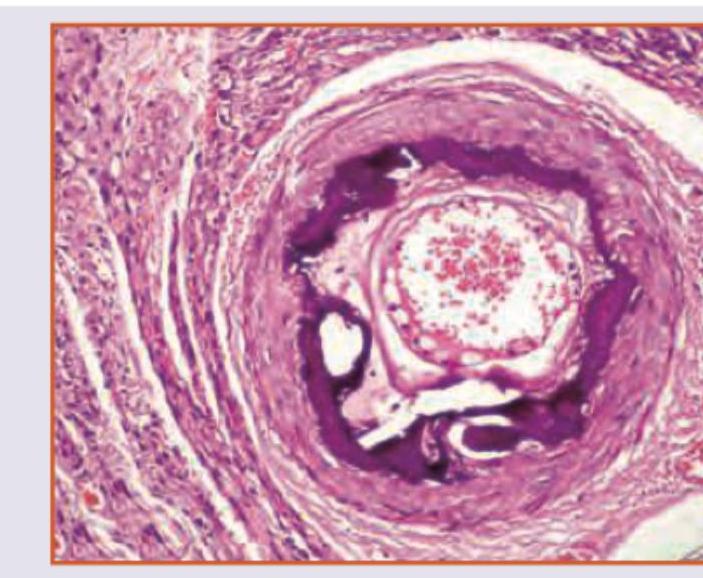

Which is true about the image shown?

Explanation: ***Monckeberg's Arteriosclerosis*** - This condition involves **calcification of the media of muscular arteries**, typically in individuals over 50 years old. - It is characterized by **ring-like calcifications** in the vessel wall, which can be seen on imaging or histology, and is usually not clinically significant as it does not narrow the lumen. *Hyaline Arteriosclerosis* - This type is characterized by **homogeneous, pink, hyaline thickening** of the walls of arterioles, with narrowing of the lumen. - It is typically seen in **benign hypertension** and **diabetes mellitus**, affecting small arteries and arterioles. *Hyperplastic Arteriosclerosis* - This condition is associated with **malignant hypertension** and is characterized by **concentric, laminated thickening** of the arteriole walls, often described as "onion-skinning." [1] - It involves proliferation of smooth muscle cells and reduplication of the basement membrane, leading to severe luminal narrowing [1]. *Fibrinoid necrosis* - This is a form of **necrosis** seen in the walls of blood vessels, characterized by deposition of **fibrin-like material** that stains intensely eosinophilic. - It is typically associated with **malignant hypertension** [2], **vasculitis**, or immune-mediated vascular damage, and is not a primary form of arteriosclerosis. **References:** [1] Kumar V, Abbas AK, et al.. Robbins and Cotran Pathologic Basis of Disease. 9th ed. The Kidney, p. 945. [2] Cross SS. Underwood's Pathology: A Clinical Approach. 6th ed. Common Clinical Problems From Cardiovascular Disease, pp. 276-277.